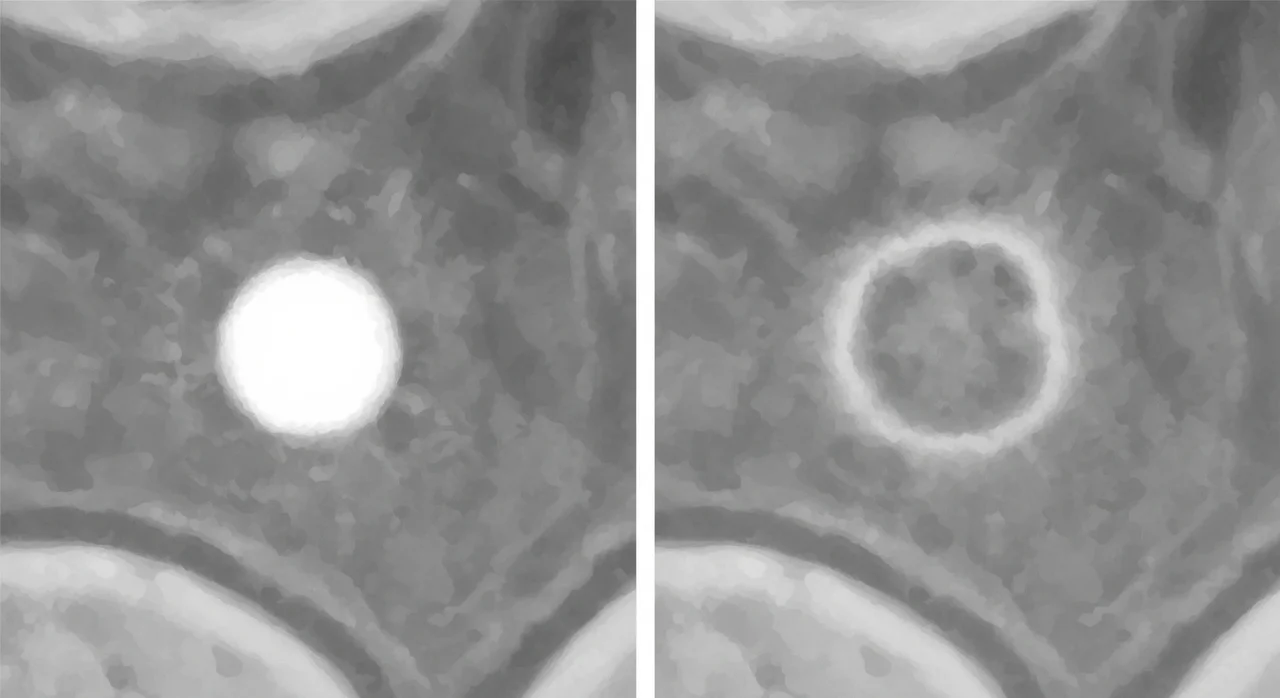

폐석회화는 폐 조직 내에 칼슘 성분이 침착되어 딱딱하게 굳어지는 현상을 말합니다. 우리 몸은 염증이 생겼다가 회복되는 과정에서 손상된 부위를 보호하기 위해 칼슘을 쌓아두는 성질이 있는데, 이것이 흉부 X-ray나 CT 촬영에서 하얀 점처럼 나타나게 되는 것입니다.

가장 많은 분이 우려하는 부분이 바로 '폐석회화가 암으로 변하지 않을까?' 하는 점입니다. 의학적으로 폐석회화와 폐암은 발생 기전과 형태가 완전히 다릅니다.

| 형태 | 경계가 뚜렷하고 딱딱함 | 경계가 불분명하고 침윤적임 |

| 밀도 | 매우 높음 (하얗게 보임) | 상대적으로 낮음 (뿌옇게 보임) |

검진 의사가 '안정된 석회화(Stable Calcification)'라고 판정했다면, 이는 암일 확률이 매우 낮다는 뜻입니다. 다만, 석회화의 모양이 불규칙하거나 주변 조직에 변화를 준다면 정밀 CT 촬영을 통해 추가 확인이 필요할 수 있습니다.